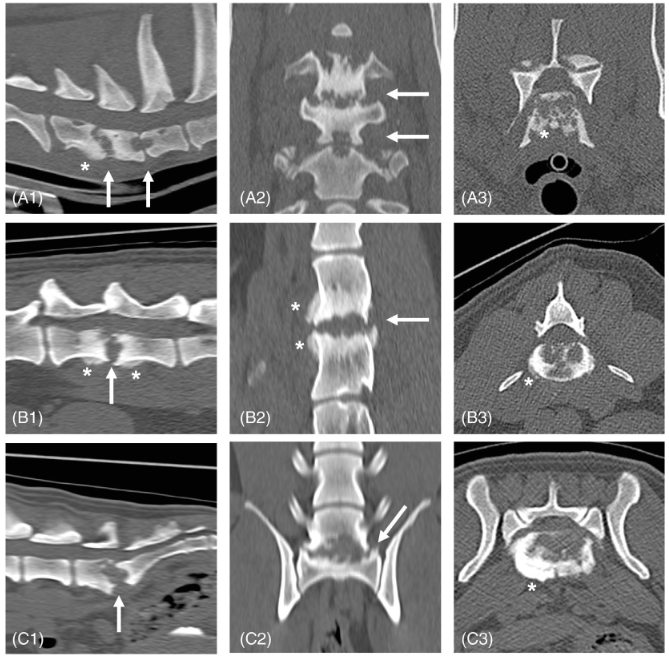

대략적으로 심한 양상으로 관찰되는 병변이 위와 같으며 종양성 골융해와 감별이 필요한데 핵심적인것이 주변의 연부조직 밀도의 종괴 병변과 부종과의 감별이 핵심 포인트.

incidental로 관찰되는 경우도 많으니 CT 의뢰를 하는 경우 반드시 기억해 둘 소견